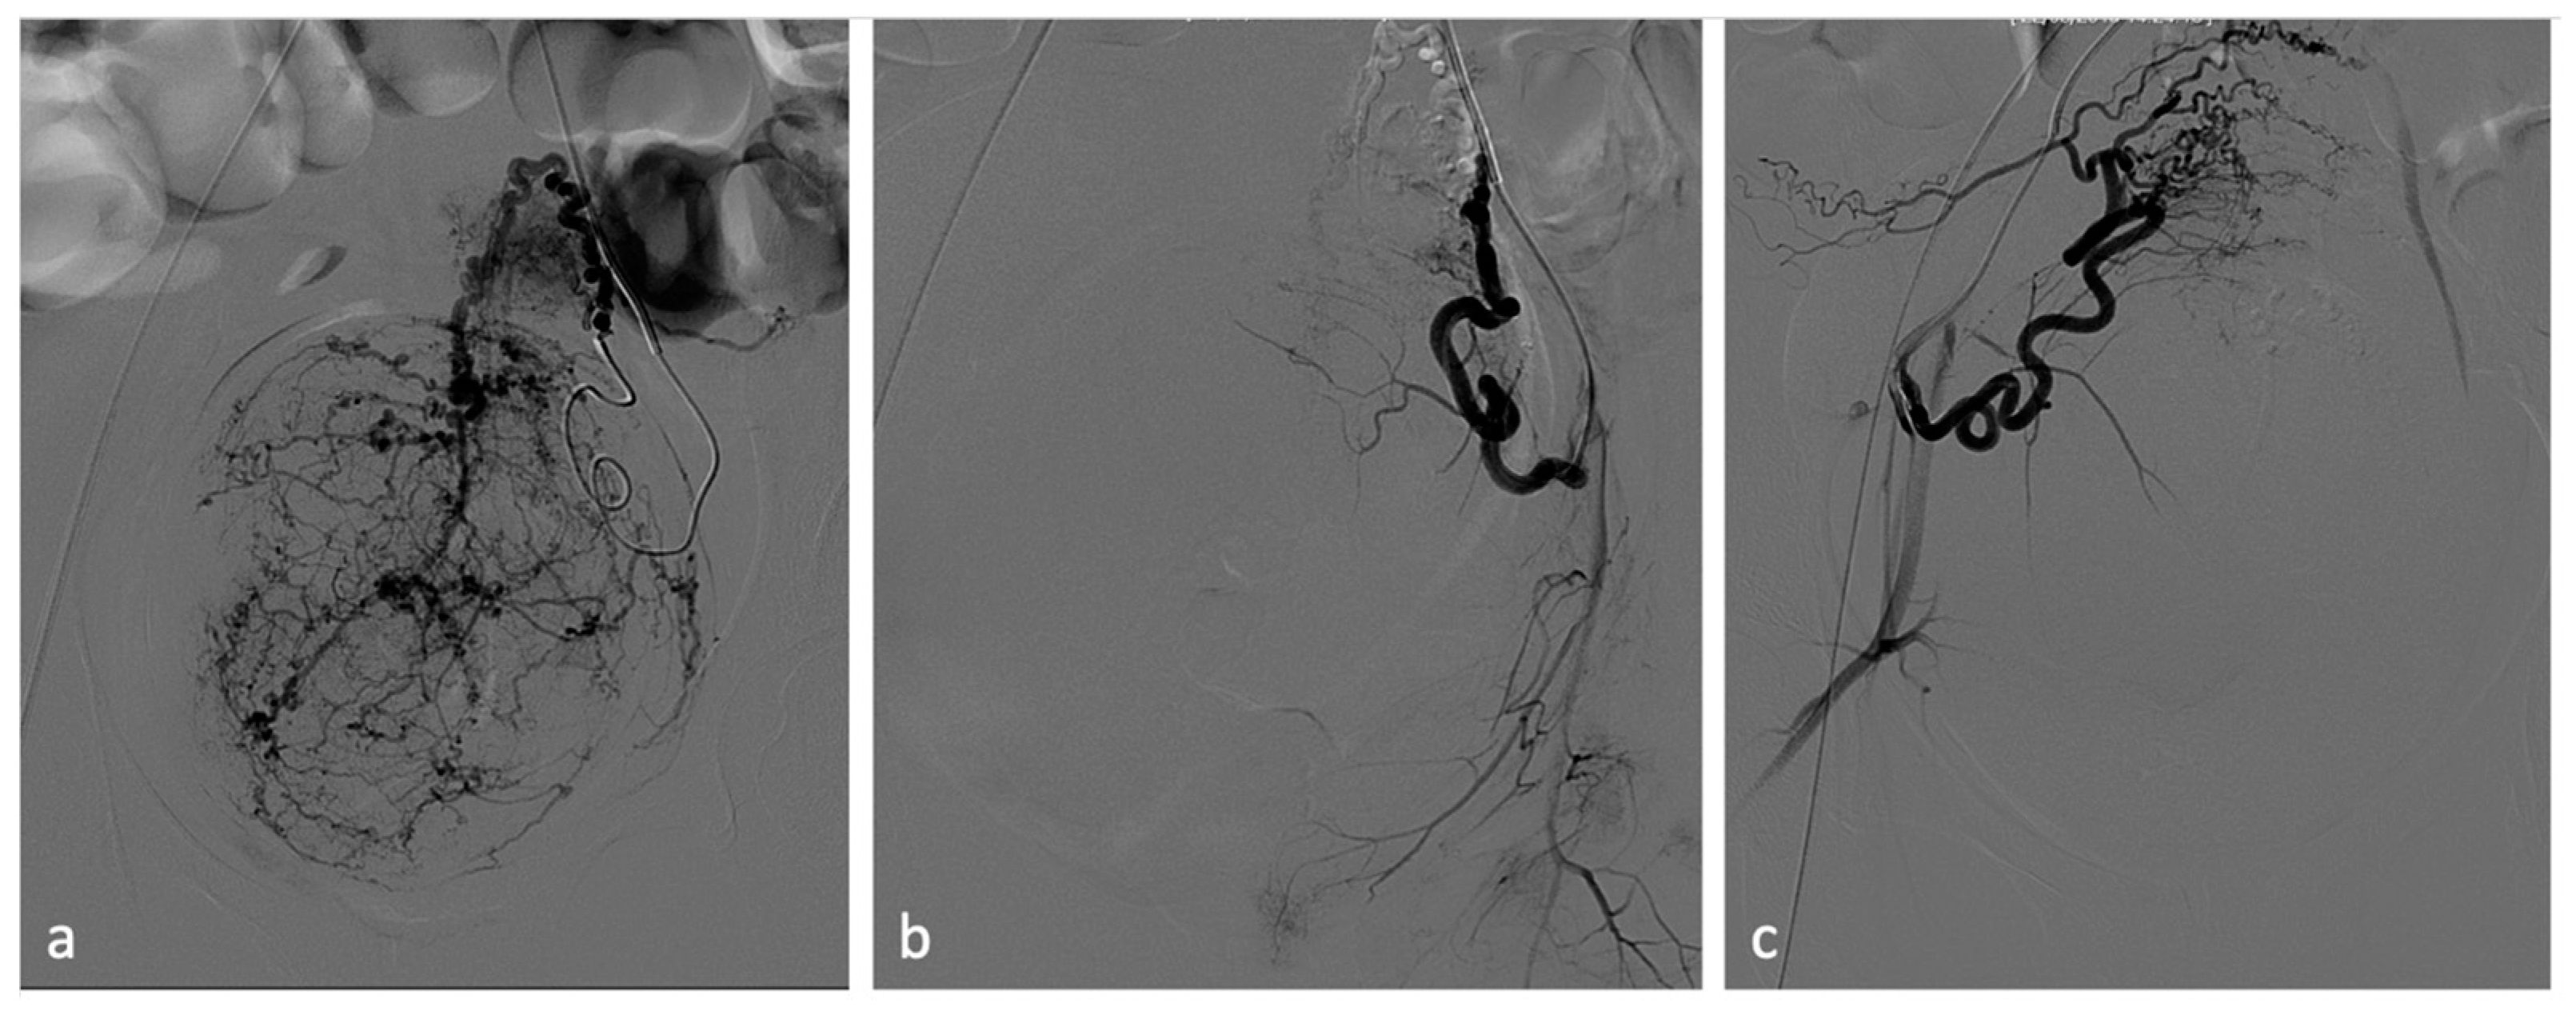

Figure 4.

Uterine artery embolization for leiomyoma. A 27-year-old patient presenting with menometrorrhagias and pelvic pain. TVUS and MRI demonstrated a voluminous isthmic uterine leiomyoma (12 cm of diameter). Selective left uterine artery arteriogram (a) shows multiple vessels feeding the large leiomyoma. Embolization through the release of embolizing microparticles was performed. Post-embolization left artery arteriogram (b) shows good devascularization of the leiomyoma. Post-embolization selective right uterine arteriogram (c) showed ectasia of the right tubal artery with origin of tubo-ovarian trunk for the ipsilateral annexal branches. Given the high risk of non-target embolization, embolization of the right uterine artery was not performed.